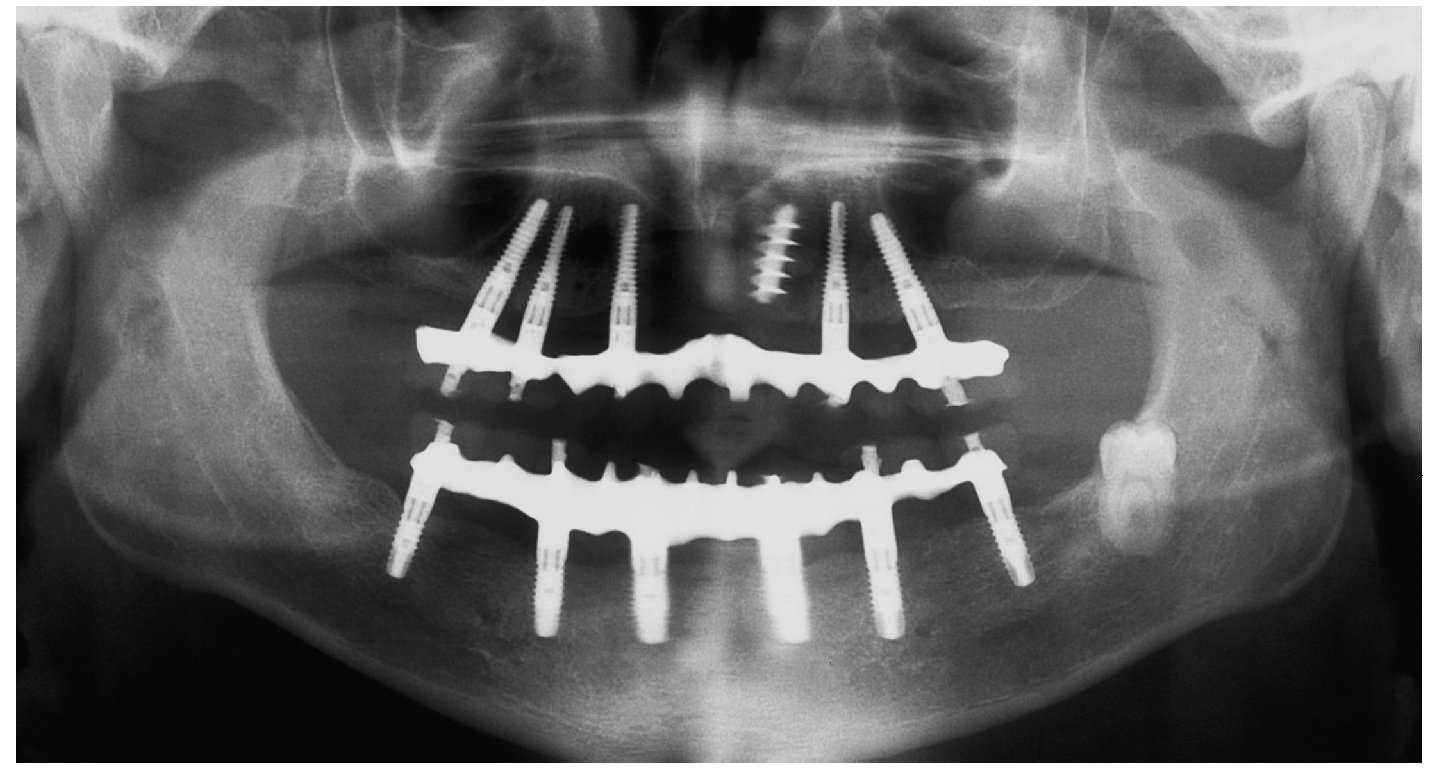

Para la rehabilitación definitiva del paciente (figs. 116 a 124) deben comprobarse de nuevo todos los aspectos de la sesión anterior y debe procederse a la cementación de las prótesis. Son indispensables controles de seguimiento a corto plazo (al cabo de 1, 3 y 5 semanas) para el ajuste óptimo de la oclusión y la comprobación de la higiene oral con una prótesis que habitualmente ofrece aberturas de acceso periimplantares más estrechas que una prótesis provisional. Tres y seis meses después de la finalización del tratamiento se deben realizar controles clínicos, y una vez al año deberían llevarse a cabo sendos controles clínico y otro radiológico.

Fig. 121. Imagen OPG de la situación final.